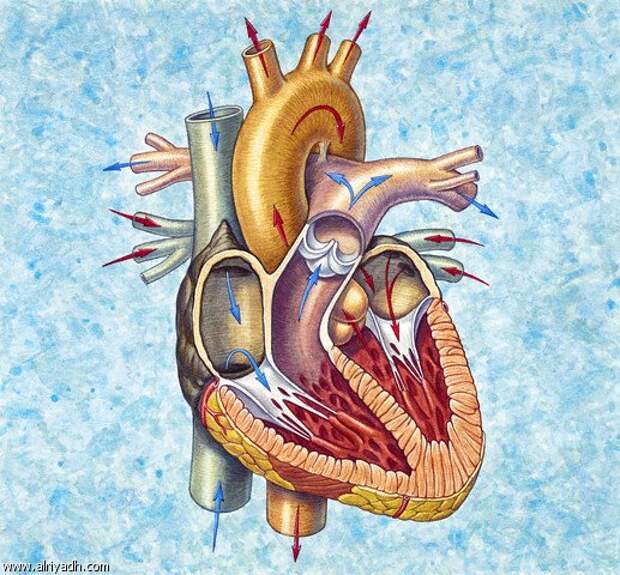

Пороки сердечно-сосудистой системы: виды и признаки